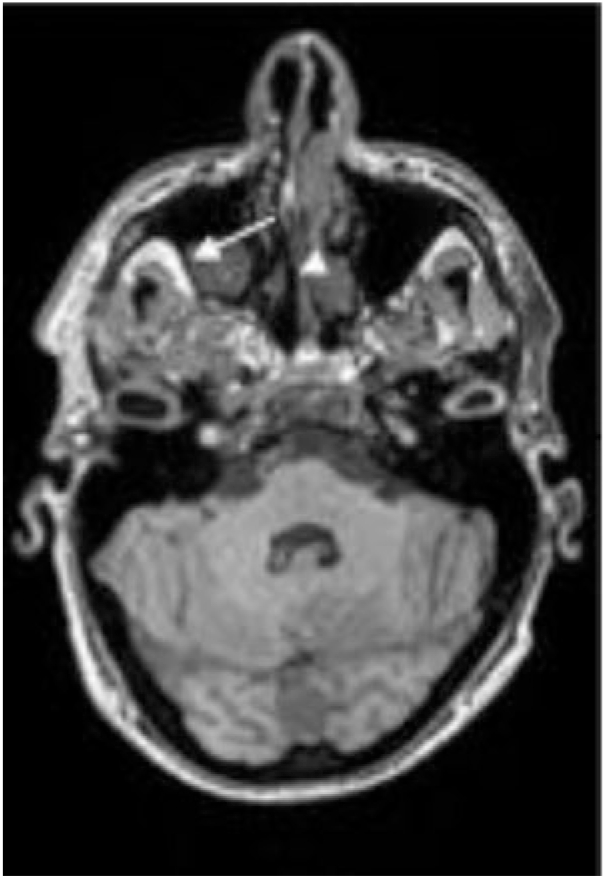

To simply give the reader a visual representation of the problem, we present the images in Figures 1–3 where accidentalomas were highlighted during some research projects conducted by our group. The research projects concerned healthy subjects and patients with schizophrenia who were investigated for relationships between cerebral activation and cognitive or emotional functioning.

Figure 2: Sagittal and axial T1 sections: Increased volume of the sella turcica (see arrow) occupied by fluid with pituitary tissue (arrow head) pressed against the sella turcica: cystic pituitary lesion or empty sella syndrome.